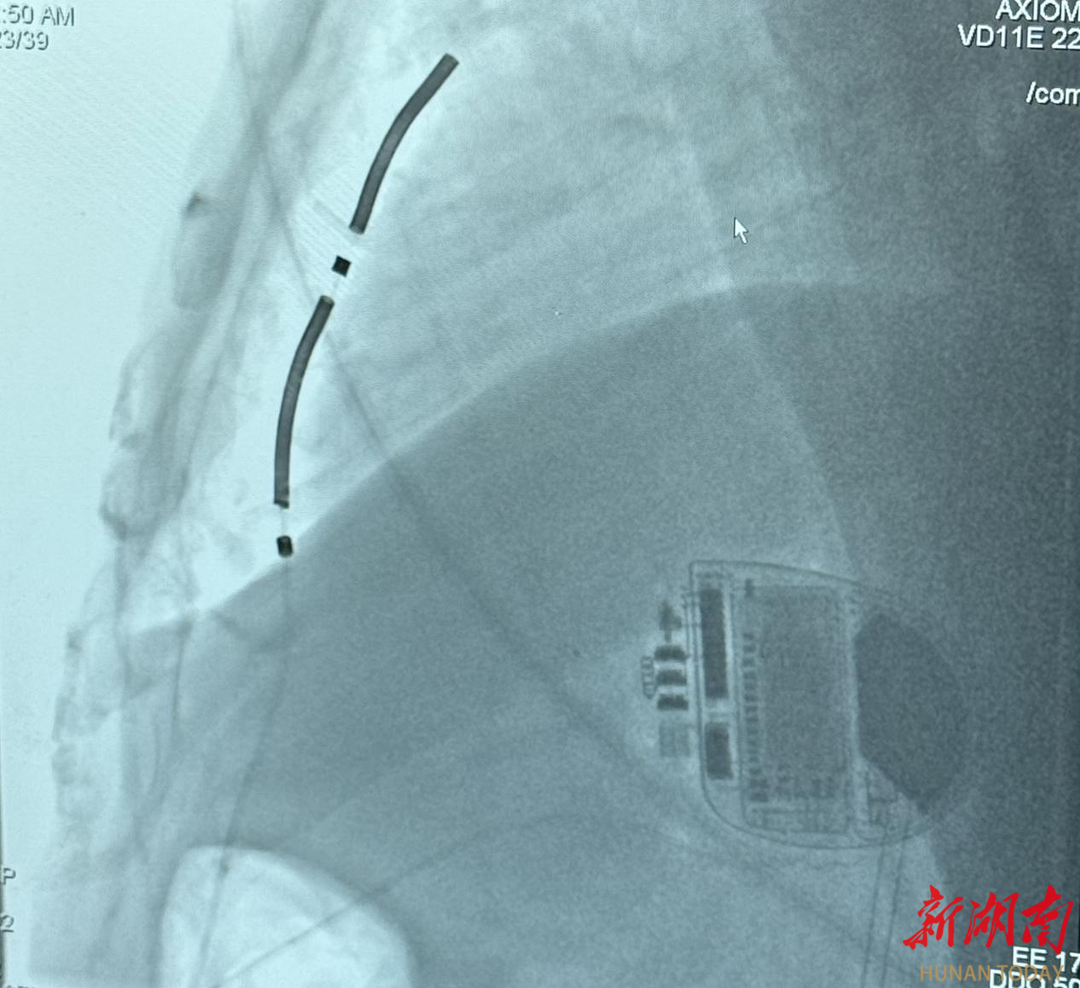

▲成功植入EV-ICD。

手术过程1小时,患者参数良好,DFT(除颤能量阈值测试)1次成功,术后患者生命体征平稳,恢复良好,安返病房。